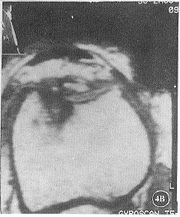

图4A,B MPR像示髌骨外侧面,股骨滑车外侧面软骨Ⅳ级退变损伤,关节镜均证 实

2.2 3D-Volume-FFE T1WI矢状位原始图像及横断位MPR图像正常髌软 骨由表及里呈高、低、高信号的平行三层结构,表面光滑,底层钙化软骨层呈线状低信号分 隔软骨和软骨下骨质(图1B)。股骨滑车软骨呈与髌软骨类似的MRI表现(图1C),仅厚度略薄 ,其中10个滑 车面软骨均匀一致变薄,信号分层特点不明显,但表面仍光滑,关节镜证实为正常软骨面。 FFE T1WI关节软骨MRI表现类似3D-Volume-FFE T1WI,但信噪比稍差,本组5例髌上囊积 液用该序列扫描,软骨与液体界面不能区分。SE-T1WI关节软骨呈高于骨皮质而低于骨髓 的中等信号,信噪比差,信号分层特点不明显,软骨与关节液界面不能确定。各序列软骨损 伤 MRI分级与关节镜分级对照见表2~4(图2~4)。